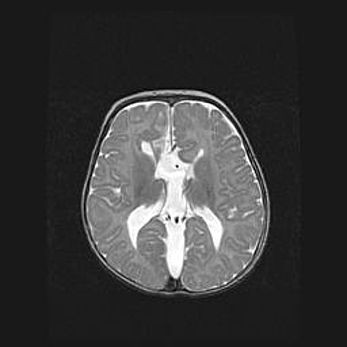

Сообщающаяся гидроцефалия. Кистозная энцефаломаляция головного мозга.

Возраст: 3 месяца 4 дня

Вес: 3100 г

Пол: женский

Окружность головы: 34 см

Срок гестации: 31 неделя

Кистозная энцефаломаляция головного мозга - одна из форм поражения головного мозга в детском возрасте. Характеризуется возникновением множественных и распространённых кист в коре, белом веществе и подкорковых образованиях головного мозга у плодов, новорождённых и детей раннего возраста. Развитие кистозной энцефаломаляции связано с внутриутробной асфиксией и гипотонией, родовой травмой, тромбозом синусов, пороками развития сосудов, инфекциями, сепсисом и другими причинами. Наиболее значимые инфекционные агенты: вирусы простого герпеса, цитомегалии, краснухи, токсоплазмы, энтеробактерии, золотистый стафилококк и другие.